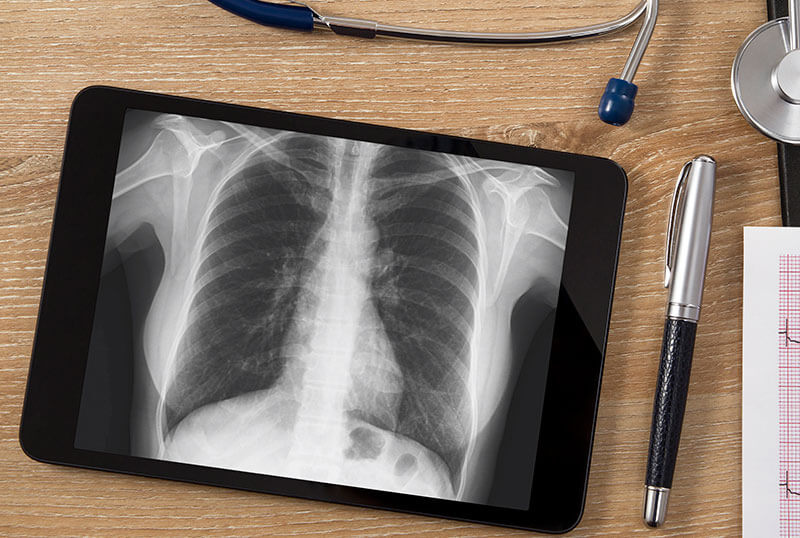

Desde su fundación, el Instituto Mexicano de Diagnóstico por Imagen ha efectuado numerosos congresos, seminarios y talleres para nuestros médicos que actualmente se preparen y deseen actualizarse en el mundo del ultrasonido.

Llámanos y solicita más información sobre nuestros servicios, ya que encontrarás cursos, diplomados, maestrías y clínica en ultrasonido. Estamos avalados por la Secretaría de Educación del Estado de Morelos y la Universidad del Estado de Guerrero; mientras que las maestría y egresos con Cédula Profesional están avalados por la Universidad de San Cristóbal de Las Casas, Chiapas, la UMA y cuentan con una duración de dos años, recibiéndose como Maestros en Ultrasonografía Diagnóstica.

¿Por qué confiar en Instituto Mexicano de Diagnóstico por Imagen? Porque brindamos una excelente atención a los médicos y un servicio eficiente totalmente personalizado. Se obtendrá un valor curricular de 1,000 horas y diplomados con duración de 18 meses.

25 años de trayectoria, combinados con los excelentes servicios que brinda el personal de Instituto Mexicano de Diagnóstico por Imagen, nos permite posicionarnos como la escuela con diplomados de ultrasonido más confiable de la región.